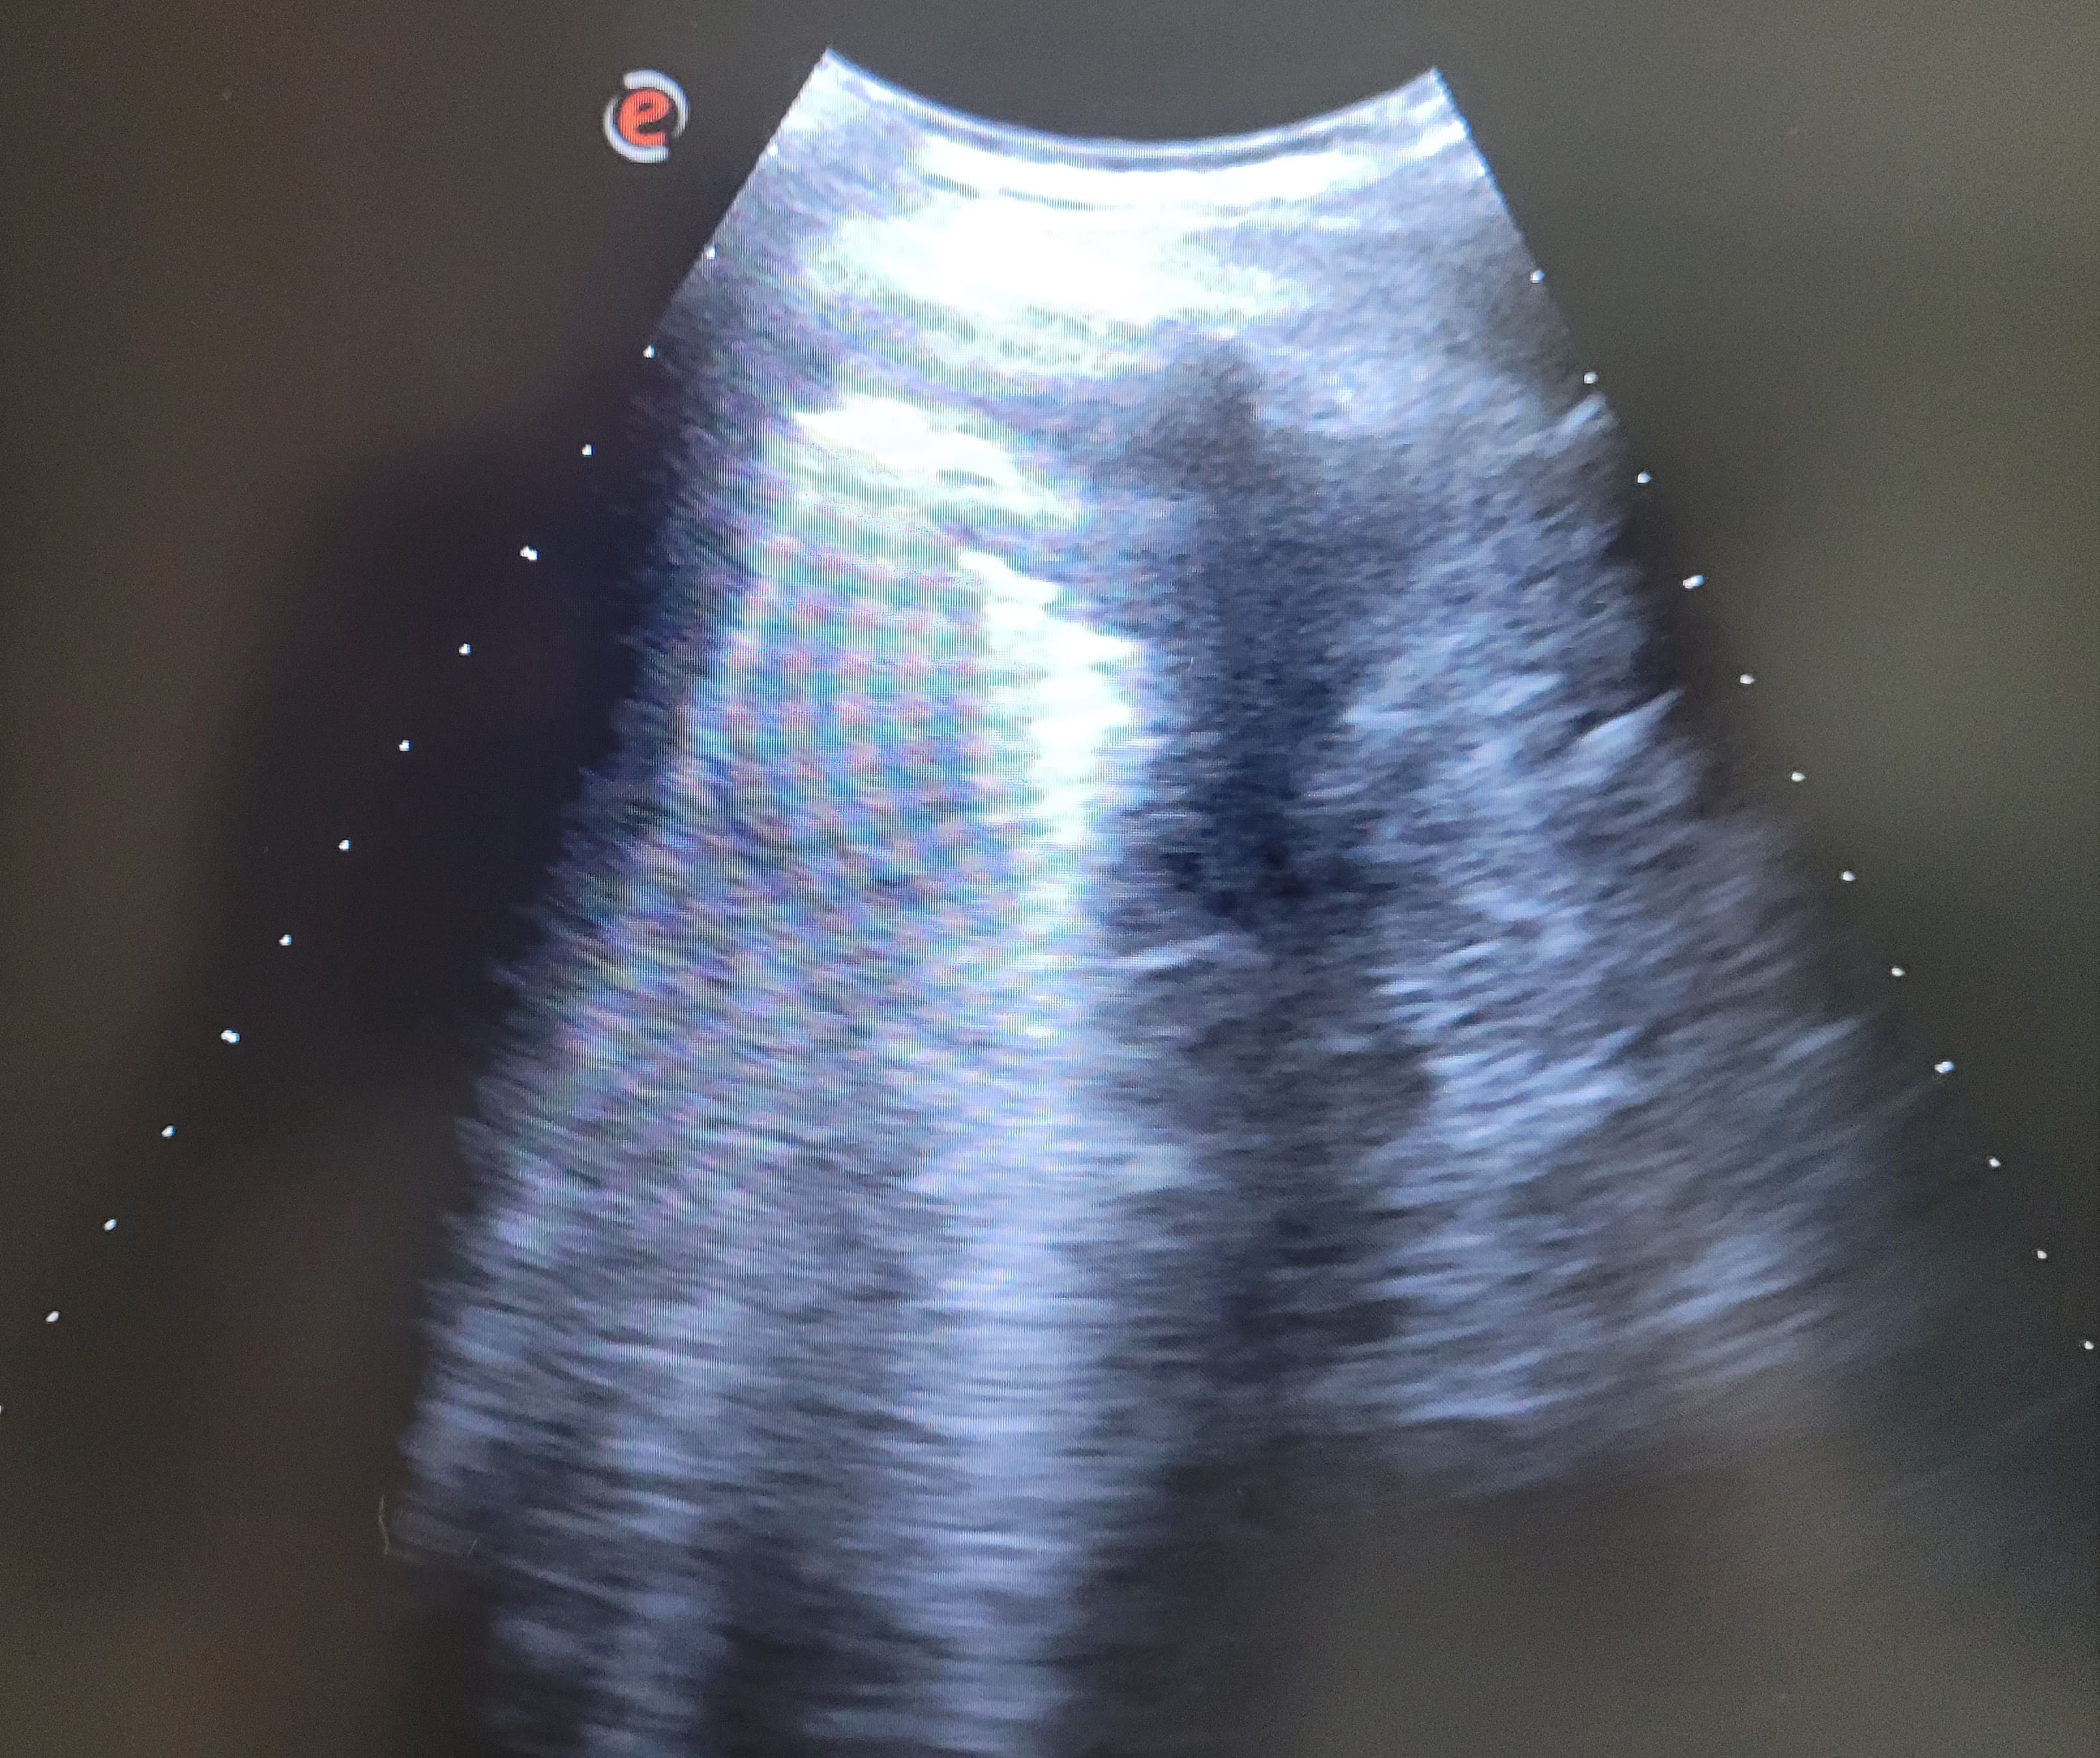

Se realiza una ecografía pulmonar, donde se observa un derrame pleural bilateral, de mayor cuantía a nivel izdo, con “signo de medusa” a ese nivel, con líneas B en áreas 6 y 12.